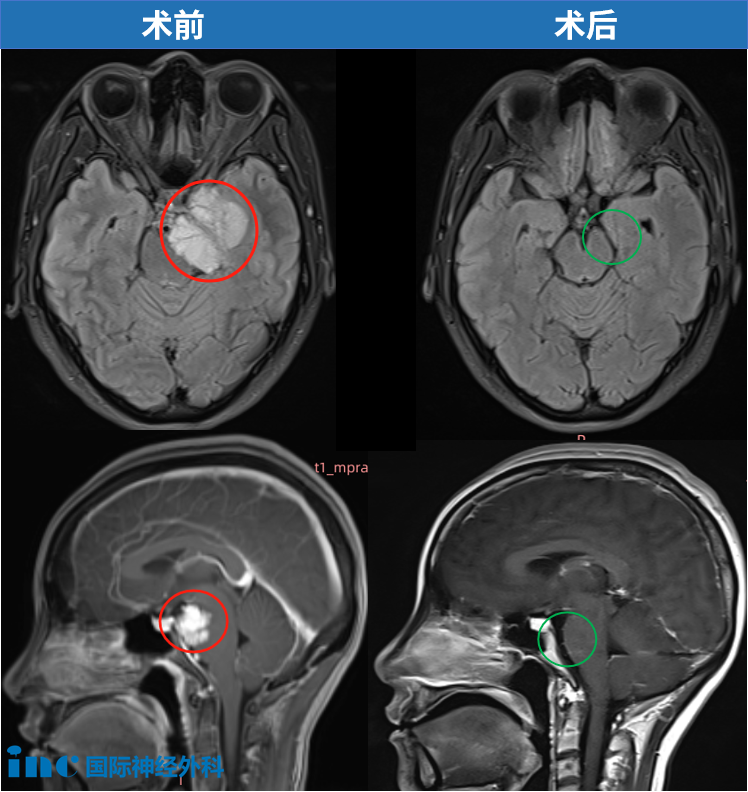

1.脑膜瘤:约1%颅内脑膜瘤起源于岩斜区,是岩斜区常见病变。它向上可侵犯岩骨尖、小脑幕、Meckel腔、鞍旁和海绵窦;向下侵犯内听道和颈静脉孔;向内侧达脑干和椎基底动脉。当肿瘤很大时,可包绕同侧Ⅲ~Ⅺ脑神经。患者临床可表现头痛、复杂的脑神经麻痹、共济失调等症状,严重者表现为偏瘫、认知功能障碍。目前,仍以手术切除为首选治疗方式。

示例1

点击阅读:天坛医院手术纪实|4.5cm脑膜瘤紧压脑干成功手术,勇敢辣妈的彪悍人生!